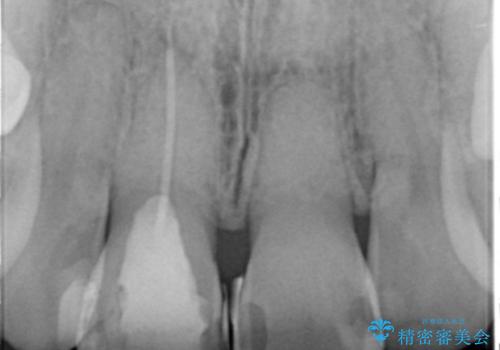

- 歯の神経を除去したのちの、変色の改善を希望され来院されました。

再度根管治療を行ったのちの、オールセラミッククラン治療を計画します。